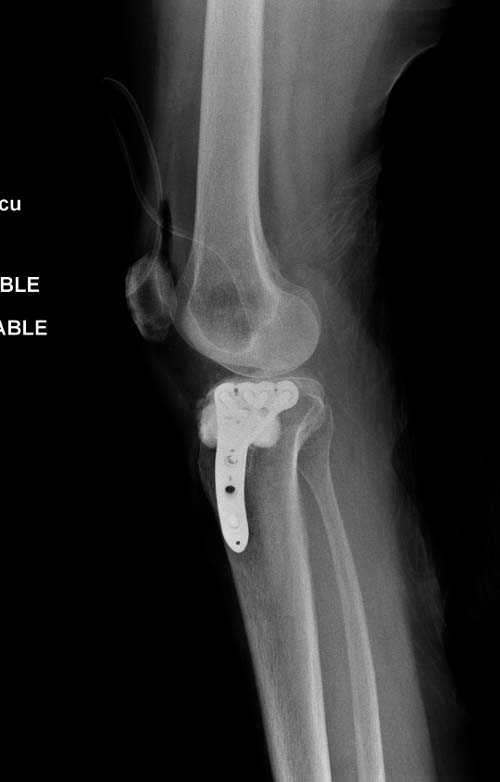

Устранение импрессии, костная аутопластика, остеосинтез опорной пластиной

задний кортекс не повреждён. Подойдёт рафтинговая пластина.

Учитывая, что у пациента молодой возраст(судя по рентгенограммам,абсолютно показано восстановление суставной линии: подменисковый доступ,подъём импренированной части мыщелка, костная аутопластика, остеосинтез, решение вопроса с мениском (шов либо парциальная резекция)).

Как подсказывают, можно с противоположной стороны приподнять сустав и заполнить костный дефект. Параллельные винты создадут достаточную опору, но иногда buttress plate за счет диафиза создает дополнительную стабильность. Структуральный материал для профилактики от раннего коллапса, и пластическим материалом служит более твердый синтетический материал (Osteoset DBM) или аутокость.